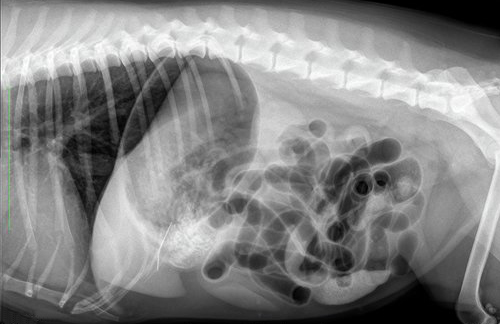

Het verhaal begint op het vakantieadres op Texel. Lady krijgt klachten van diarree, braken en ze is erg ziek. Bij de dierenarts worden vervolgens röntgenfoto’s gemaakt. Het is de verdenking dat ze ziek is geworden door het drinken van zeewater en het zand dat ze heeft binnengekregen, maar er is nog iets anders te zien; een langwerpige structuur.

Het baasje van Lady vindt het fijn als zijn eigen dierenarts ook naar de röntgenfoto’s kijkt en stuurt de foto’s naar ons. We staan zelf ook even te kijken over wat er op de foto te zien is. Ondertussen knapt Lady behoorlijk op en komt de eigenaar naar huis.

Ter controle, of de structuur nog in de buik aanwezig is, worden opnieuw röntgenfoto’s gemaakt. Hierop is het voorwerp nog goed zichtbaar, met een soort oogje erin. Het moet dus een naald zijn. De foto’s suggereren verder dat de naald niet in het maag-darmstelsel zit, maar in de buikholte.